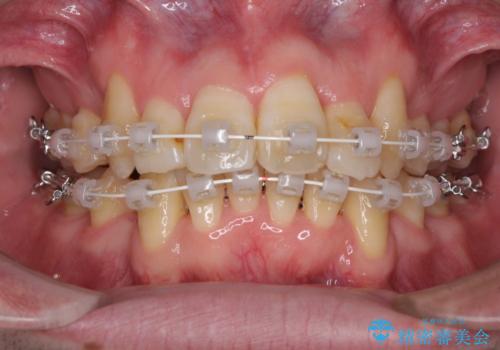

- 矯正装置

- 審美装置

治療開始直後は、あっという間に歯列が整い、すぐに終わるのではないかと思われましたが、治療の後半にブラックトライアングル解消のための処置を行ったため、当初予定していた2年半ほどの期間を要することとなりました。